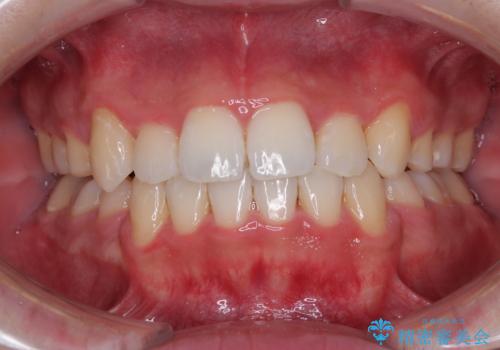

前歯の歯列が整ったことで、歯磨きが大変やりやすくなり、患者様には大変満足していただけました。